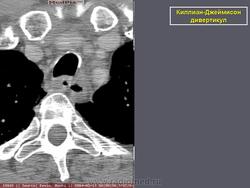

Киллиан – Джеймисон - дивертикул

Случай 2: сагиттальная КТ

Случай 2: осевой КТ

Киллиан – Джеймисон - дивертикул.